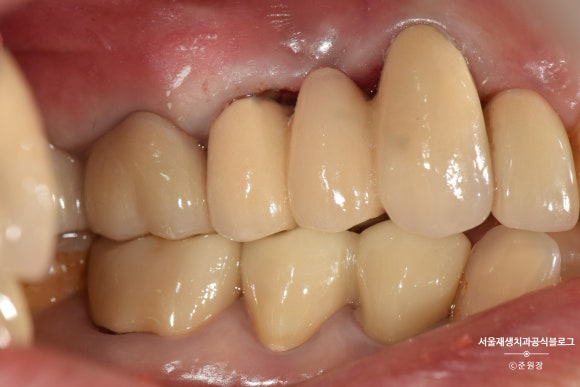

또 다시 1주일 뒤, 최종보철물 결합

처음부터 치아 사이 사이 공간이 넓은 분이셔서,

기왕 하는 김에 치아 사이 공간도 매꿀 수 있겠냐고 물어보셨습니다.

인접 치아에 연결된 미니 브릿지를 만들어서

보다 심미적인 결과를 도출해낼 수 있었습니다.

치아 재식 직후>

치료 후>